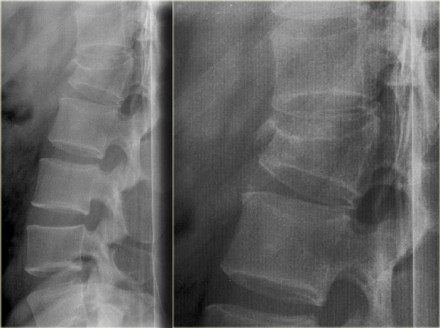

On the left images of a 31 year old male.

He was working on a roof, fell approximately 5 meters landing on his feet.

He complained of pain in left lower extremity and lower back.

First study the images, then continue reading.

On the x-ray there is a hyperflexion injury of L1 with

involvement of the anterior column and possible involvement of the

middle column.